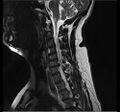

الانزلاق الغضروفي العنقي

يحدث الانزلاق الغضروفي العنقي، غالبًا بين الفقرات العنقية الخامسة والسادسة (C5–6) والسادسة والسابعة (C6–7). هناك قابلية متزايدة بين المرضى الأكبر سنًا (60+) للفتق في الجزء العلوي من العنق، وخاصة في الفقرات العنقية الثالثة والرابعة.[23] قد تظهر أعراض الانزلاق الغضروفي العنقي في الجزء الخلفي من الجمجمة والعنق وحزام الكتف ولوح الكتف والذراع واليد.[24] قد تتأثر أعصاب الضفيرة العنقية والضفيرة العضدية.[25]

- التصوير بالرنين المغناطيسي هي الدراسة المعيارية الذهبية لتأكيد الاشتباه في انزلاق غضروفي. مع دقة تشخيصية تبلغ 97%، فهي الدراسة الأكثر حساسية لتصور الانزلاق الغضروفي بسبب قدرتها الكبيرة على تصور الأنسجة الرخوة. كما يتمتع التصوير بالرنين المغناطيسي بموثوقية أعلى بين المراقبين مقارنة بوسائل التصوير الأخرى. ويشير إلى انزلاق غضروفي عندما يظهر إشارة متزايدة مرجحة بـ T2 عند المنطقة الخلفية التي تغطي 10% من القرص. وقد أظهرت أمراض الانزلاق الغضروفي ارتباطًا بتغيرات النوع 1 من مقياس موديك. عند تقييم اعتلالات الجذور العصبية القطنية بعد الجراحة، فإن التوصية هي إجراء التصوير بالرنين المغناطيسي مع التباين ما لم يكن هناك موانع أخرى. يعد التصوير بالرنين المغناطيسي أكثر فعالية من التصوير المقطعي المحوسب في التمييز بين الأسباب الالتهابية أو الخبيثة للانزلاق الغضروفي. يُشار إليه في وقت مبكر نسبيًا في مسار التقييم (<8 أسابيع) عندما يظهر المريض مؤشرات نسبية مثل الألم الشديد والعجز الحركي العصبي ومتلازمة ذيل الفرس. التصوير الموتر الانتشاري هو نوع من تسلسل التصوير بالرنين المغناطيسي المستخدم للكشف عن التغيرات الدقيقة في جذر العصب. قد يكون مفيدًا في فهم التغييرات التي تحدث بعد أن يضغط القرص القطني المنفتق على جذر العصب، وقد يساعد في التمييز بين المرضى الذين يحتاجون إلى تدخل جراحي. في المرضى الذين لديهم شكوك عالية في اعتلال الجذور العصبية بسبب الانزلاق الغضروفي القطني، ومع ذلك فإن التصوير بالرنين المغناطيسي غامض أو سلبي، يوصى بدراسات التوصيل العصبي.[44] توفر الصور المرجحة الناتجة عن التصوير بالرنين المغناطيسي (T2) تصور واضح لمادة القرص البارز في القناة الشوكية.